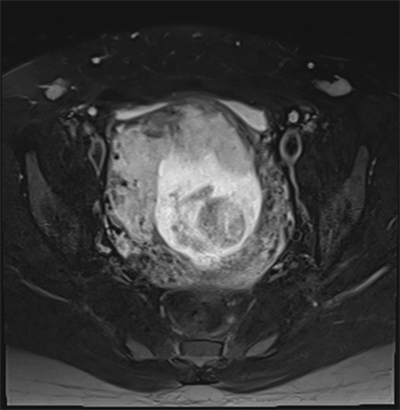

On 16/6/2021, MRI was done without dye and reported a cervical ectopic pregnancy 15 weeks gestation totally present in cervical canal, Figure 3. The placenta was located at the anterior and right lateral aspect of the cervical wall, with marked stretching, thinning of the underlying myometrium and focal interruptions of the myometrial line together with significant contour bulge (suggestive of placenta accreta spectrum, increta subtype), there were markedly increased regional vascularity and blurring of the urinary bladder wall but no evidence of gross intravesical extension. Prominent vascularity is also noted all over the cervical and peri-cervical regions, Figure 4. The main uterine cavity proper showed no sacs and the uterus showed two fibroids, the largest (3 × 3 cm) located at the upper aspect of the anterior uterine wall and having sub-mucosal extension.

Figure 4. T2 weighted MRI image in transverse plane, showing focal interruptions of the myometrial line together with significant contour bulge suggestive of placenta increta, there were markedly increased regional vascularity and blurring of the urinary bladder wall but no evidence of gross intra-vesical extension.